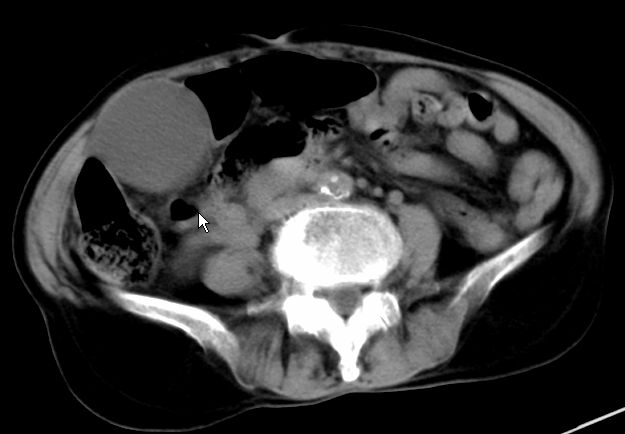

以下是引用zjzjr在2008-12-16 12:49:00的发言:[br]肝内外胆管全程扩张,胆囊明显增大,未见占位征像.建议mrcp.

以下是引用jiangjing在2008-12-16 13:19:00的发言:[br]肝内外胆管全程扩张,胆囊明显增大,扩张胆总管下段径较中上段小,未见胰管扩张,提示胆总管远端梗阻伴感染.建议增强及mrcp 检查

以下是引用朱亮在2008-12-16 12:54:00的发言:[br]胆总管远端应薄层扫描 胆总管逐渐变细 考虑胆系慢性炎症